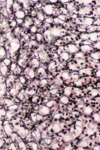

What type of cells can be seen in this image?

Active fibroblasts (seen coming away from ECM which indicates that they are active)